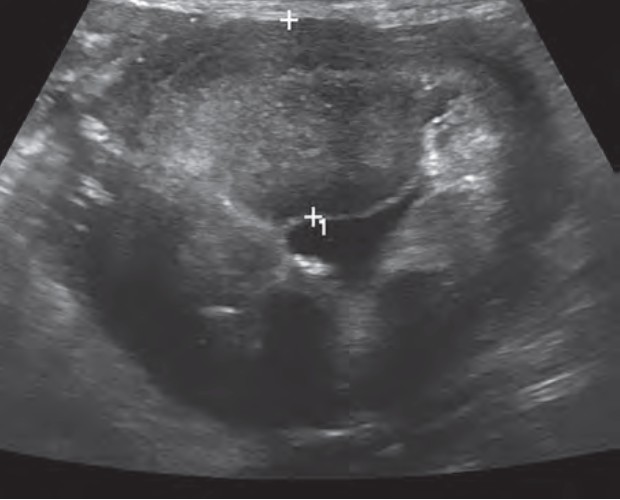

- 腹部超声:可能会看到胃壁增厚或腔内肿块,还可以识别出肿大的淋巴结或其他器官的异常。腺癌通常固定在幽门窦的小弯侧,累及胃壁全层(图1)。平滑肌肉瘤通常位于黏膜下,更常出现在贲门附近。

图1. 胃腺癌的超声图像,显示胃窦部有一个肿块。在幽门的胃窦部,靠近黏膜处,有一个大约2×3厘米的管状肿块,呈显著高回声,伴有低回声斑驳。